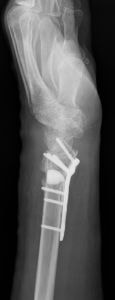

橈骨遠位端関節内粉砕骨折の術前(上)と術後(下)

橈骨遠位端骨折は、通年ですべての年齢層において最も多い上肢の骨折の一つです。骨折の主な原因は、転倒や高所から転落して手をつくことですが、手を強く捻って受傷することもあります。本骨折は、ケガの仕方、外力の大きさや骨の強さにより折れる場所や折れ方に様々なタイプ(型)があるのが特徴であり、尺骨や手根骨の骨折、手関節の靭帯損傷や神経障害を合併することもあります。

治療法は、骨折の型、骨折の徒手整復の可否、そして合併症の有無により異なり、比較的軽いものには保存的治療が、変形が大きかったり粉砕していたり骨折が関節内に及ぶ重症例には手術が行われてきました。しかしながら、近年は一人暮らしのご高齢の方の増加により、さほど重症でない骨折に対しても、早期から手の使用を可能とし、後遺障害を少なくするために手術を行うことが多くなってきています。

手術には、経皮的に鋼線を刺入して固定するピンニングや骨折部を直視下に整復してプレート固定する観血的手術があります。術後には早期の機能回復を目的としてリハビリ(作業療法)を行うことがあります。

橈骨遠位端変形治癒骨折の術前(左)と術後(右)